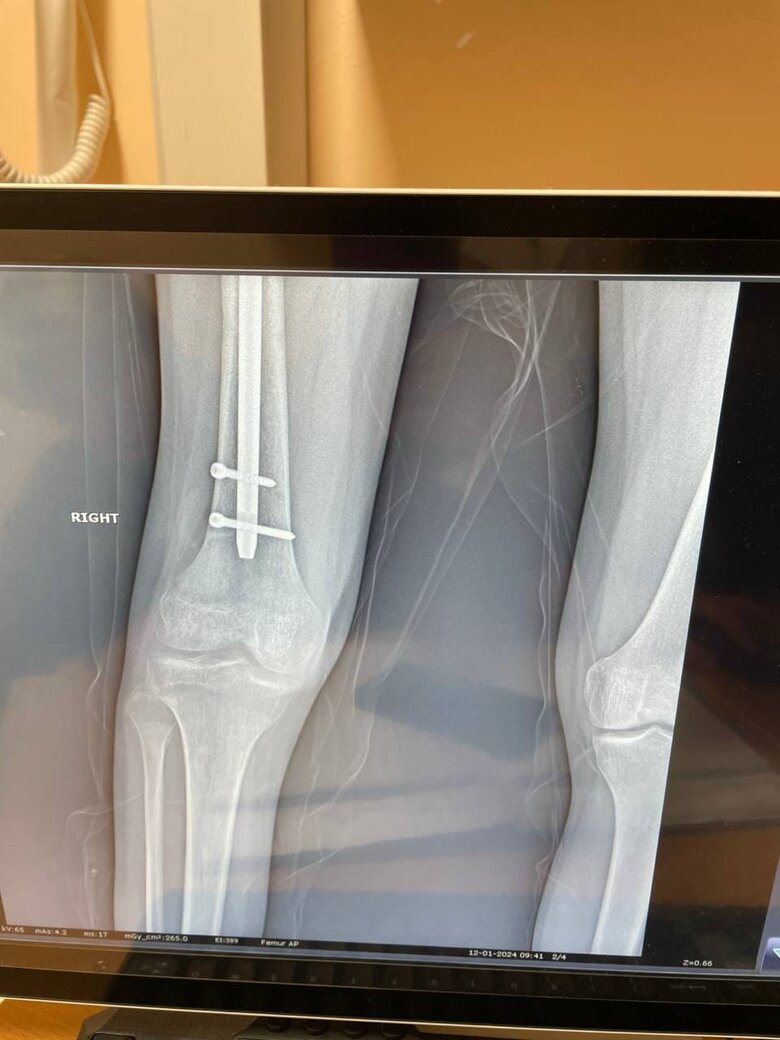

Друзі, знайомтеся: це Алік. Мій боєць, сапер, який отримав важкі поранення влітку минулого року під час штурмової операції південніше Бахмуту. Операція пішла невдало, групу накрили гради. Алік врятував кількох поранених бійців, надавав їм першу допомогу, але й сам зазнав серйозних ушкоджень.

Військовий третьої штурмової бригади Алік